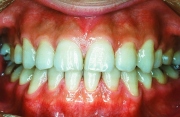

治療前

治療後